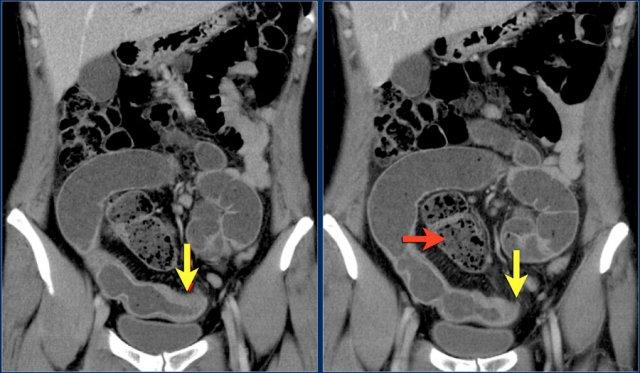

Các hình ảnh cho thấy u carcinoid biểu hiện là một khối tăng sinh mạch (mũi tên đỏ) với phản ứng xơ hóa desmoplastic (mũi tên vàng).

Đây là hình ảnh điển hình của u carcinoid biểu hiện là một khối mạc treo lớn với phản ứng xơ hóa desmoplastic và co kéo các quai ruột non lân cận kèm dày thành ruột (các mũi tên).

Khối nhỏ trong lòng hồi tràng (mũi tên vàng). U carcinoid ruột non kèm theo khối mạc treo dạng tua gai với phản ứng xơ hóa desmoplastic lân cận.